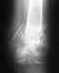

Место пореза давно зажило, но оно (и вокруг) багрово-синюшного цвета, сильно припухло. Кожа там возвышается над плоскостью ногтя на 4-5 мм. Палец весь отёчный. Ногтевой сустав могу согнуть (вроде как связки целые), но только чуть-чуть, из-за отёка. Второй сустав сгибаю посильнее, но также из-за отёка, не более, чем на 30...35 град. ТРАВМА: Месяц назад порезал палец острым "мясным" (свинина) ножом, 1-я фаланга, между основанием ногтя и суставом. Боюсь, что даже мог полоснуть и по кости. Рану не обработал. Ночью сильно болело. Наутро сильный отёк. Потом перешёл на соседние 2 пальца и на кисть. ЛЕЧЕНИЕ: 3...13 день - перорально антибиотик Супракс. К 6-7 дню отёк кисти и соседних пальцев прошёл, но на пальце остаётся и сейчас. 14...19 день - 5 раз УВЧ, толку нет, отёк тот же. 6 раз запаривал, по совету врача - толку не было. с 21 дня - перорально Ципролет (7 суток) ; "Амикацин", в/м , 7 суток по 2 укола ; с 30 дня - перорально Амоксиклав, 2 таб./сутки В течение всего времени применял мази: Вишневского, левомеколь, диоксидиновая ИССЛЕДОВАНИЯ: Снимок на 20-й день. Заключение рентенолога - "выраженный остеопороз ногтевой фаланги и дистального отдела средней фаланги. Остеомелит ногтевой фаланги 1,2 стадии". СОСТОЯНИЕ: Первые 3...4 дня иногда ощущал то "в жар", то "озноб". Потом прошло. Стойкого повышений температура у меня за всё время не было. Нормальная и сейчас. Рана чуть-чуть гноилась, на 12 день всё зажило. Но отёк пальца остался до сих пор. С е й ч а с в пальце постоянных дергающих болей нет, указывающих на активный гнойный процесс нет. Только иногда чувствую покалывания в месте пореза. Оно (и вокруг) синюшного цвета, припухло. Кожа там возвышается над плоскостью ногтя на 4-5 мм. Палец весь отёчный. Ногтевой сустав могу согнуть (вроде как связки целые), но только чуть-чуть, из-за отёка. Второй сустав сгибаю посильнее, но также из-за отёка, не более, чем на 30...35 град. 1. Что это может быть? Какой диагноз ? 2. Может ли из-за остеомиелита так долго держаться отёк ? 3. Как лечить ? 4. Когда отёк начнёт уменьшаться ? 5. Когда отёк исчезнет совсем, чтобы я смог сгибать палец полностью хотя бы во втором суставе ? Заранее благодарен.